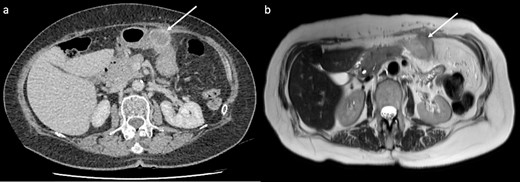

CT showed a 32 mm cystic enhancing lesion contacting both the anterior abdominal wall and greater curvature of the stomach (Fig. 1a). Magnetic resonance imaging (MRI) suggested that the mass was more likely solid than cystic. It was hyperintense on T2 imaging, predominantly isointense on T1 imaging, and showed peripheral enhancement in the early arterial phase without restricted diffusion or significant internal debris (Fig. 1b). A fluorodeoxyglucose (FDG) positron emission tomography scan showed that the mass was lobulated with heterogenous peripheral FDG uptake. CT head and chest were normal. Gastroscopy and mucosal biopsy showed a submucosal mass along the greater curvature of the stomach without mucosal breach, suggesting origin from the abdominal wall. Endoscopic ultrasound was performed with fine needle biopsy. Histopathology showed poorly differentiated malignancy, and immunohistochemistry confirmed a phenotype consistent with metastatic PDAC.

CT and MRI of the lesion (arrows). (a) CT showed a 32 mm cystic enhancing lesion between the anterior abdominal wall and mid greater curvature of the stomach. (b) The lesion appeared hyperintense on T2 imaging and predominantly isointense on T1 imaging, without significant internal debris.